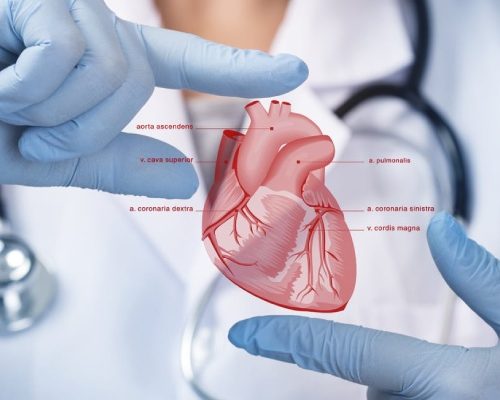

Cardiology

Innovation meets cardiovascular trial expertise.

Cardiovascular clinical trials, no matter their size, demand a specialized, experienced cardiovascular CRO to help you navigate the path to success.

With unmatched cardiovascular trial experience and new approaches fueled by data and analytics, Mediclin Clinical Research brings agility and speed to trials large and small.